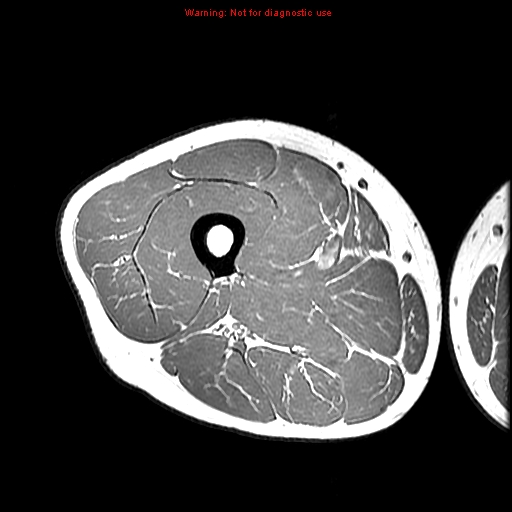

rectus femoris

vastus medialis muscle

vastus lateralis

vastus intermedius

sartorius muscle

femoral artery

adductor longus

adductor brevis

adductor magnus

gracilis muscle

gracilis muscle gluteus maximus

gluteus maximus

biceps femoris (long head)

biceps femoris (short head)

semimembranosus

semitendinosus

semitendinosus sciatic nerve

sciatic nerve

common fibular nerve

tibial nerve